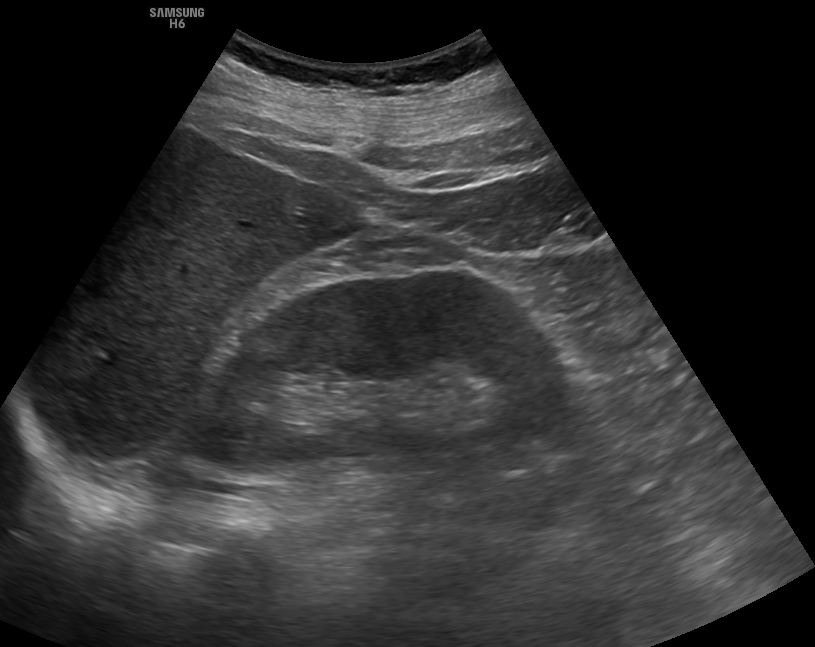

Persistiendo el dolor, se realiza ecografía clínica objetivándose: vejiga con abundante contenido urinario, con sensibilidad a la palpación y sin deseo miccional. Riñones de morfología y ecoestructura normal, sin signos de hidronefrosis. Hígado y vesícula sin alteraciones, sin litiasis y Murphy ecográfico negativo.

Ante los hallazgos, se plantea la posibilidad de retención aguda de orina (RAO). Este caso ilustra cómo la presentación clínica de la RAO puede simular un cólico nefrítico u otras causas de dolor abdominal agudo.

La ecografía clínica resultó decisiva al identificar una vejiga distendida sin signos de obstrucción a nivel renal, permitiendo un diagnóstico rápido y un tratamiento inmediato.

Es una herramienta fundamental para la evaluación del dolor abdominal, especialmente en pacientes mayores con clínica inespecífica. Su uso permite optimizar el diagnóstico y mejorar el manejo terapéutico, como en este caso de retención aguda de orina de presentación atípica.